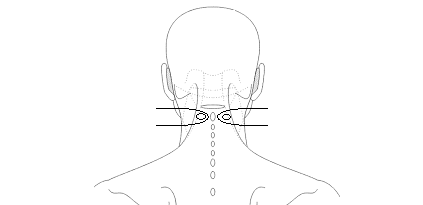

neck.png 가운데 손가락 끝을 목 뼈 뒤 돌기 옆에 마주 대고 고개를 뒤로 젖힌다